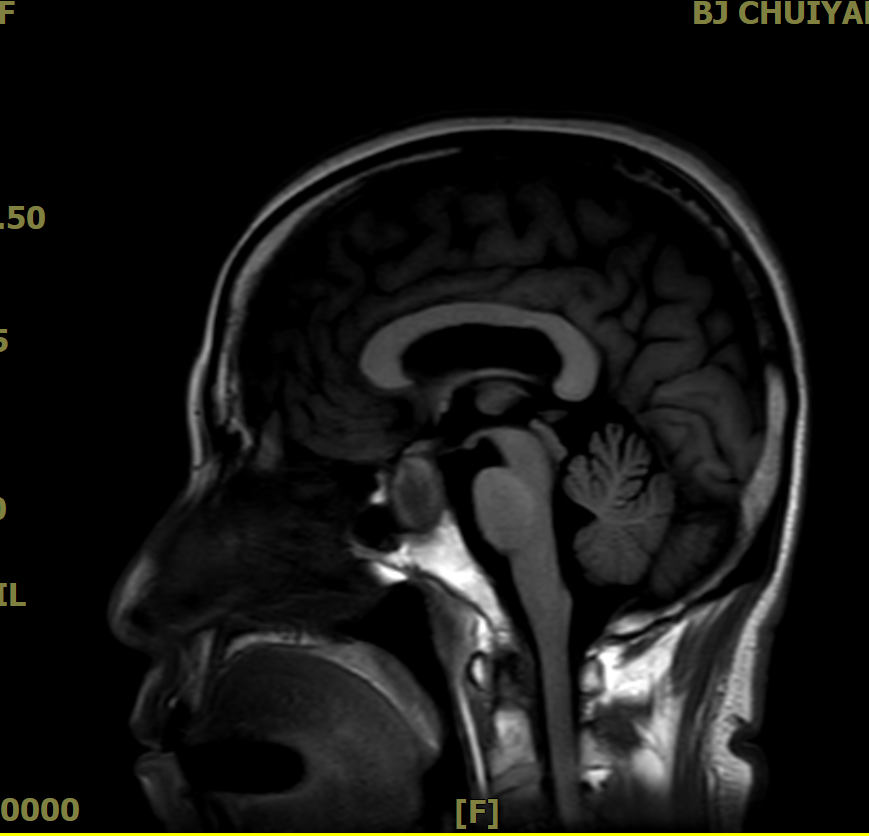

·鞍区MRI平扫+增强:诊断的“金标准”,清晰显示肿瘤大小、位置及与周围结构关系。